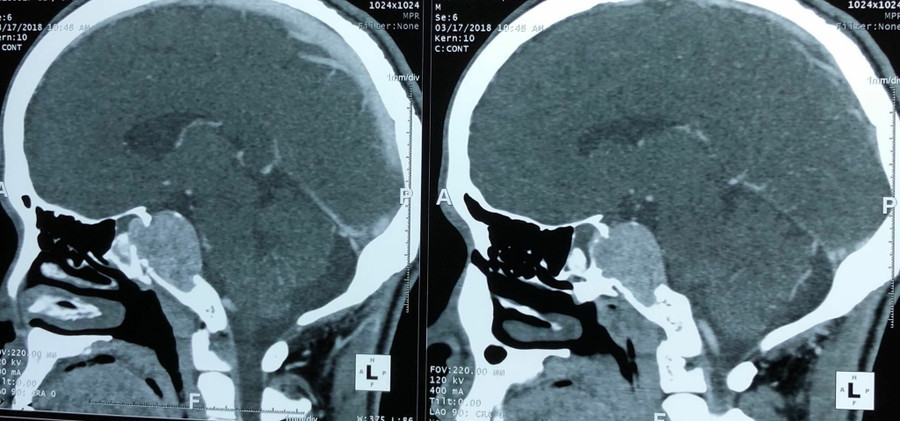

Đến khi không thấy có dấu hiệu thuyên giảm, bệnh nhân có biểu hiện đau đầu thường xuyên hơn thì mới nhập viện. Sau khi khám, chụp cộng hưởng và làm các chỉ định tại bệnh viện K, kết quả cho thấy có khối u não nền sọ vùng dốc nền có kích thước lớn 3 x 4cm.

| Phim chụp khối u |